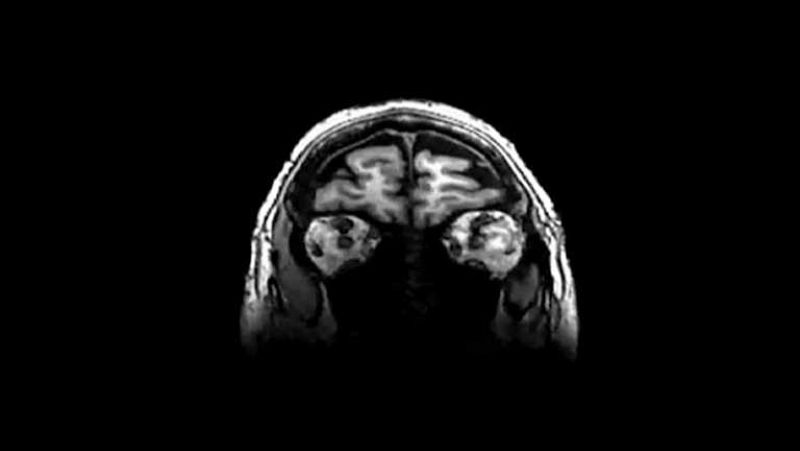

Hoy sabemos, o al menos es lo que afirma un estudio publicado en la revista americana Cell, "Célula", que somos como somos por un error genético, por la duplicación de un gen que provocó la evolución del cerebro de nuestros más lejanos ancestros.